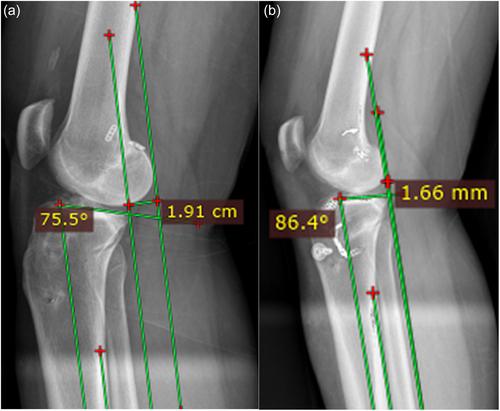

An institutional review board-approved retrospective study of all patients who underwent a revision ACLR using a BPTB autograft, ACWPTO and LET from a single centre from 2018 to 2023 was performed. Inclusion criteria were patients >18 years of age with a failed ACLR, posterior tibial slope (PTS) of >15°, previous ACL-tunnel diameters of <14 mm, and intact ipsilateral patellar tendon. PTS and anterior tibial translation (ATT) were measured using the mechanical axis on long weight-bearing lateral tibial radiographs.

Nine patients, all men, were evaluated with a mean age of 31.1 years and a mean follow-up of 31.4 months. The PTS significantly decreased from 16.8° (range: 15.1°–18.9°) preoperatively to 9.3° (range: 5.0°–14.7°) post-operatively (p < 0.001) and ATT significantly decreased from 14.6 mm (range: 10.7–19.0 mm) preoperatively to 6.3 mm (range: 1.3–11.5 mm) post-operatively (p < 0.001). Preoperatively, all patients showed significant instability with the Lachman test Grade 2/3 and the pivot shift test Grade 2/3. Post-operatively, Lachman test grade was 0 and Pivot shift test grade was 0 in all patients (p < 0.01), and the average post-operative subjective International Knee Documentation Committee (IKDC) score was 79.4 (range: 60.9–95.4).